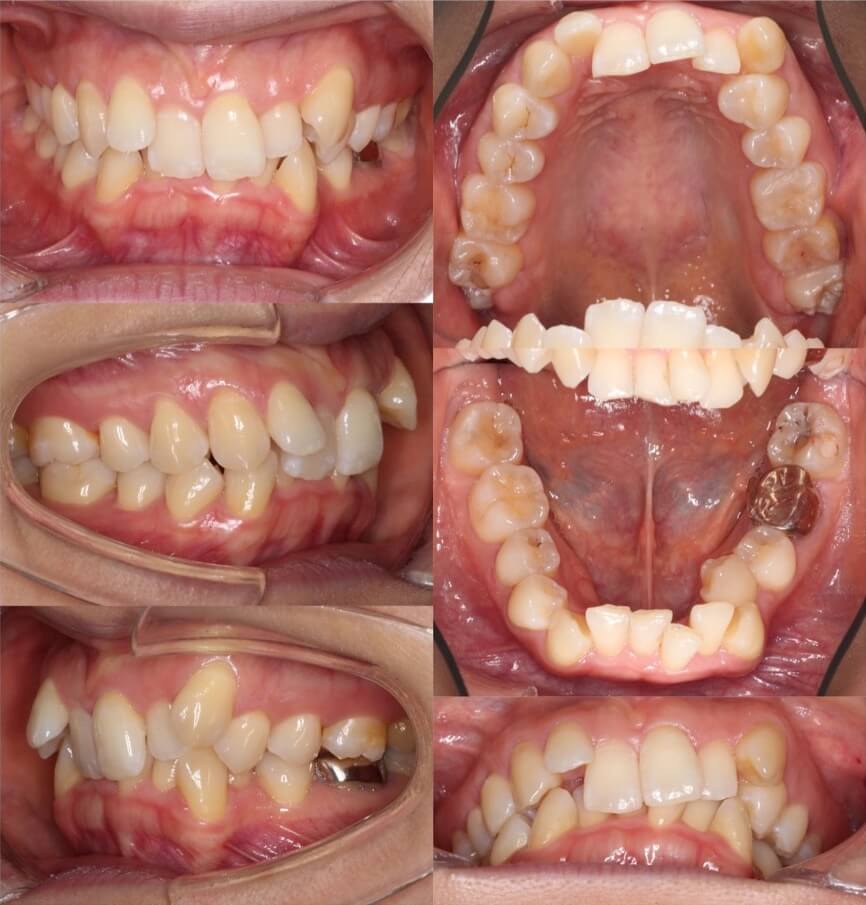

20代女性・マウスピース型装置・1本抜歯

II級2類と呼ばれる、過蓋咬合を伴う上顎前突症例です。歯並びのスペース不足に左右差があったため、左上のみ小臼歯を抜歯しています。上下顎前歯の前歯を前方に傾斜移動させた反作用で過蓋咬合を改善させています。

<症例概要>

主訴:歯並びのがたつき

住まい:千葉県船橋市

年齢・性別:20代女性

症状:上顎前歯舌側傾斜・過蓋咬合・上下顎叢生・左4番シザーズバイト

治療方針:抜歯空隙閉鎖

治療装置:マウスピース型矯正装置(アライナー装置)

抜歯:左上5番

治療期間:2年5か月

アライナー枚数:60+37+24ステージ (7日交換)

リテーナー:上下フィックスタイプ+クリアタイプ

治療費用:990,000(税込)

代表的副作用:痛み・治療後の後戻り・歯根吸収・歯髄壊死・歯肉退縮